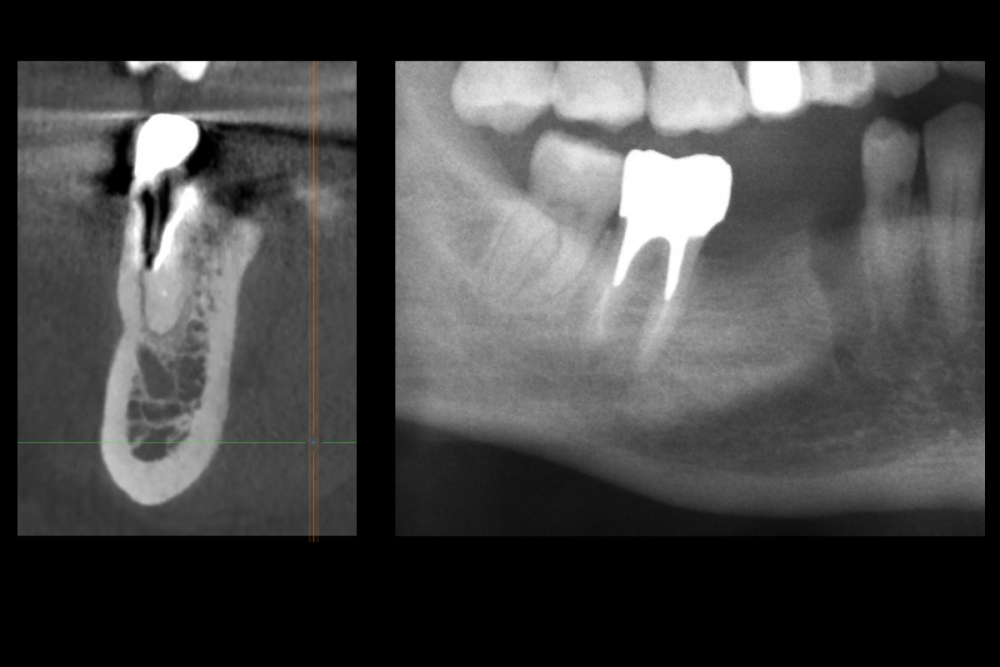

Карен Аванесов Опубликовано 16 июля, 2021 Поделиться Опубликовано 16 июля, 2021 Вариант герметизации послеоперационной раны, когда, хочется установить имплантат и сократить для пациента сроки реабилитации. Итак, "Астра" отличные имплантаты при хороших условиях работают, при экстремальных ситуациях выбор калибров сильно страдает и суживает возможности оператора (очевидно менеджерам не интересно будущее системы, эксклюзивная цацка профайл и маркетинговое продвижение на "озоне" это не то), как по мне, раздутый, абсолютно не удобный хирургический набор, не разделяю восторгов относительно эксклюзивности и предписуемым волшебным свойства, кость наросла! это только на "астре" так или только на анкилозе! На любой системе можно получать результаты. Представляю клинические случаи с одинаковыми условиями, но разными системами, там где "астра" не захотела первичной стабильности, в виду недостаточно широкой талии, "дентиум" диаметром 6мм встал бы на ура, но "астра" такой заказ ортопеда. 8 1 1 3 Ссылка на комментарий

Карен Аванесов Опубликовано 21 февраля, 2022 Автор Поделиться Опубликовано 21 февраля, 2022 Дозрела костна ткань. Возвращаясь к вопросу о "волшебстве" брендовых систем.... Безусловно, молодому специалисту, через сопливый нос бубнить на консультации что от СТАВИТ страуманн, мобель или аштру, поднимает самомнение, окрыляет, иногда и до звездной болезни, помогает быстрее "заматереть,"но сути не меняет. Кость "подрастает" не только аштре например, что иногда демонстрируют с восторгом, но и на отстойном дентиуме тоже, и думаю и на отстойной альфа-био и т.д., т.е. все-же от условий зависит, пациента и конечно техника, что там как и дальше будет. Соберу кейс покажу вошебный рост на голых витках корейского народного ширпотреба)))) 1 Ссылка на комментарий